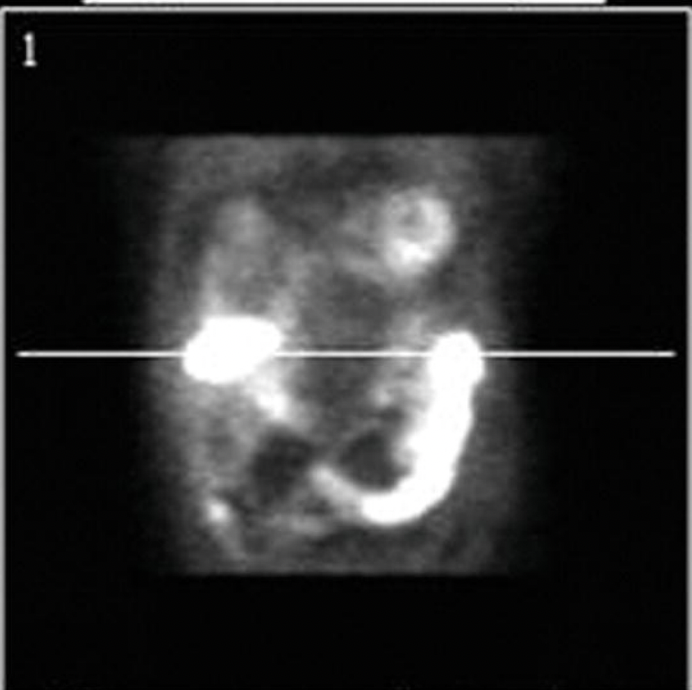

Q

An 85-year-old male with moderate CAD documented 6 years ago presents with atypical chest pain. An exercise stress SPECT MPI is performed and the short-axis view is shown in Figure . Which coronary artery is likely to be causing the symptoms?

RCA